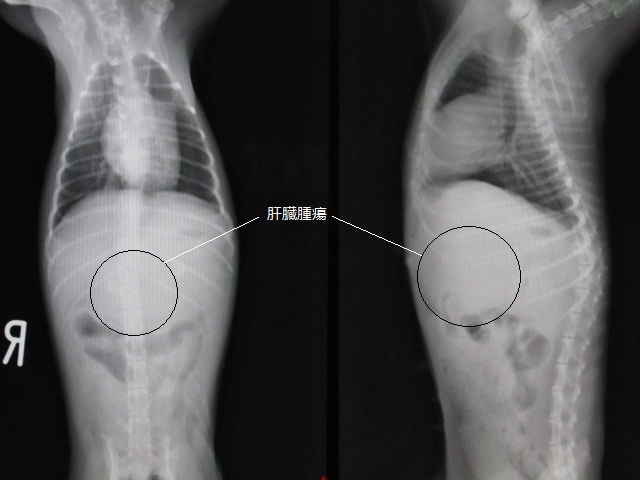

術前のレントゲンです。

肝臓のあたりが不鮮明です。